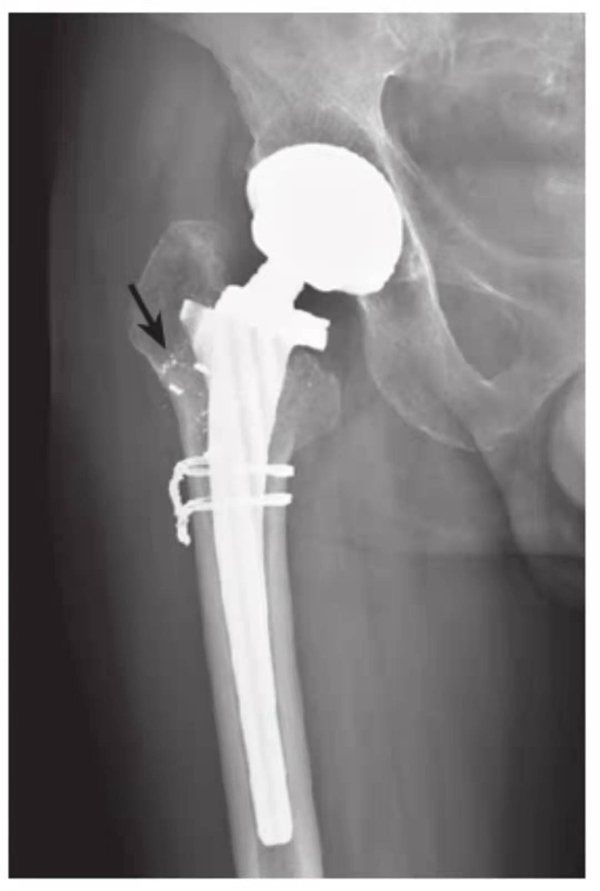

图10 假体柄断裂

平片,示左侧假体柄上段断裂错位,同时近端假体周围骨质吸收